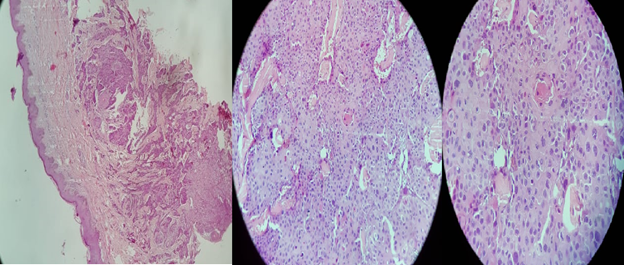

A biopsy was done which confirmed their metastatic nature (Figure 3). The patient was scheduled to receive palliative chemotherapy. However, he died 4 weeks after the initial diagnosis.

Figure 3 Cutaneous infiltration by a well differentiated keratinizing squamous cell carcinoma which may be consistent with metastases of squamous cell carcinoma or urothelial carcinoma with squamous differentiation of the urinary tract.